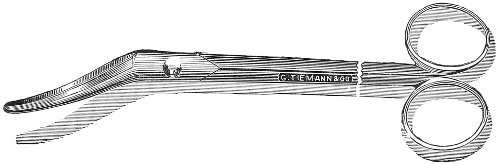

Fig. 24.—Emmet’s perineal scissors.

Fig. 25.—Curved scissors for denuding.

The secondary operation is performed at any time after cicatrization has occurred—often many years after the receipt of the injury. This operation is at present one of the commonest in gynecology, because the injury is not detected, is neglected, or is improperly repaired after labor. In the secondary operation an anesthetic is necessary. The mucous membrane must be removed or denuded on the posterior wall and about the mouth of the vagina, in order that the lacerated structures may be brought again in apposition. The denudation is best made by means of scissors curved on the flat (Figs. 24 and 25).